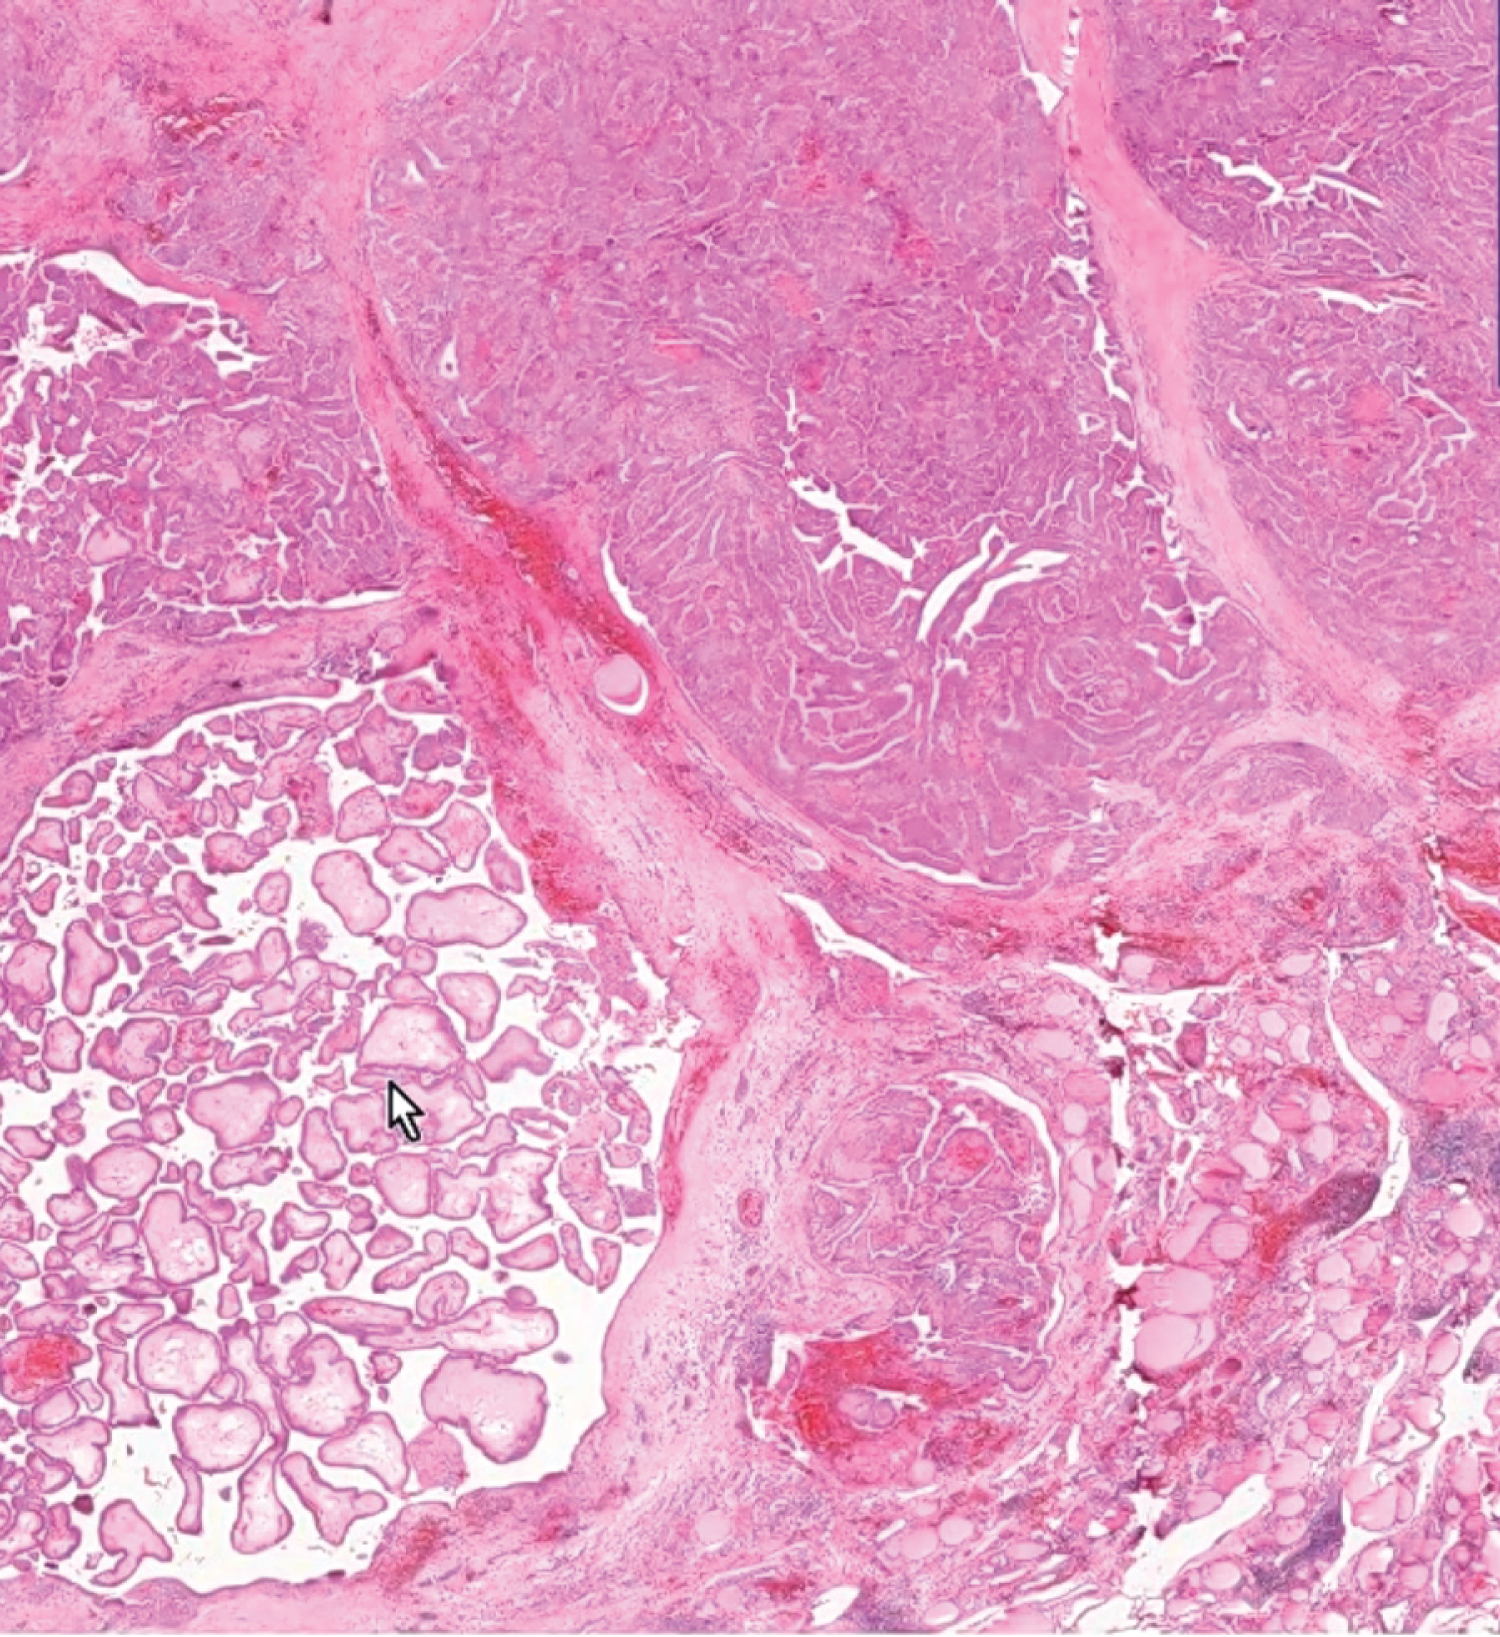

A 55-year-old female patient presented with a swelling in the front and sides of the neck (Figure 1) for last 1 year which was initially increasing slowly in size but for the last 5 months, the patient noticed that the swelling was rapidly increasing in size. She was complaining of dull aching pain over the swelling for last 3 months. She also complained of slight hoarseness of voice for last 2 months. She had slight difficulty in swallowing and breathing. There were no symptoms suggestive of hypothyroidism or hyperthyroidism. On examination, general survey was essentially normal. On local examination of the thyroid region, there was non-uniform diffuse enlargement of the thyroid gland; right lobe being more enlarged than the left lobe. The surface was nodular, hard in consistency, moving up and down with deglutition, mobile and not fixed to the skin and underlying structures. There were no signs of toxicity. Multiple lymph nodes were palpable in the right deep cervical group at levels II and III. The lymph nodes were firm in consistency and mobile. Systemic examination was normal. Investigations suggested a diagnosis of papillary carcinoma of thyroid and a surgical excision was performed. Histopathology confirmed the diagnosis of papillary carcinoma of thyroid (Figure 2).

Figure 2: Histopathological examination of the excised specimen showing multiple papillae (white arrow) along with fibrous tissue separating bands of the tumour. View Figure 2